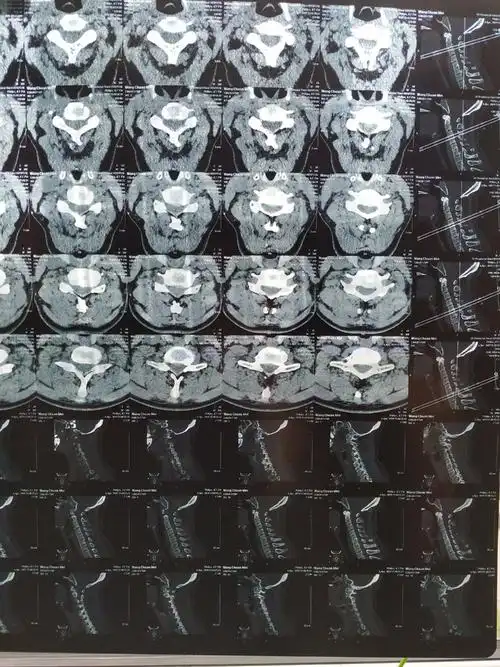

拍的颈椎ct说有一块弯曲了,如何治疗?